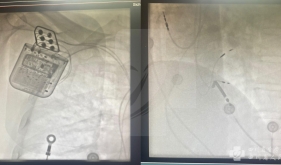

2017年7月我院独立成功完成西南地区首例永久起搏器择性希氏束起搏导线植入术,后期随访持续保持良好状态,实现了安全而稳定的“人造房室结...